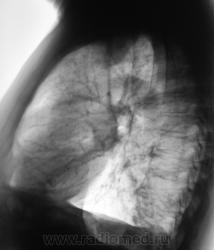

Осумкованный плеврит. Надеюсь, с ребрами там все в поряде?

Согласен но для спокойствия глянул бы на скопии.

Какие мнения будут?

Дела плевральные.Или осумкованный гидроторакс, или мезотелиома... Прошедшие годы, видимо, уже расставили точки над "i"?

Осумкованный плеврит.